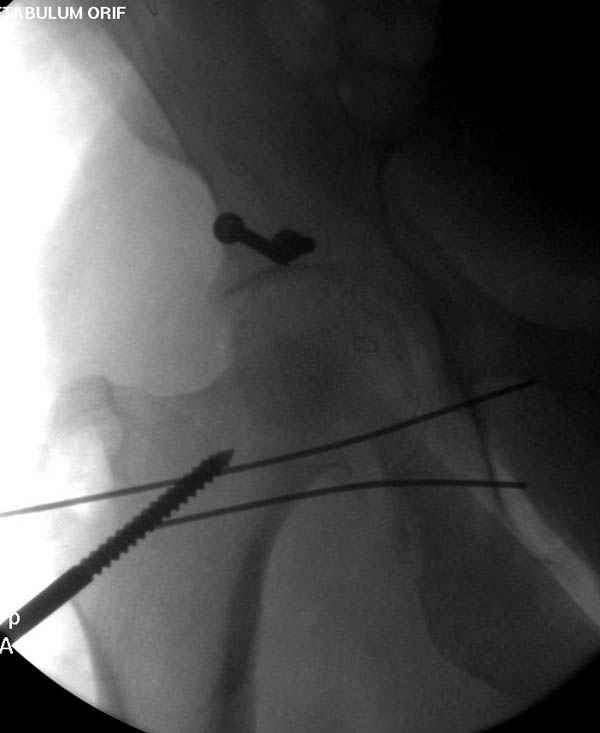

По возможности вышлите снимки, сканы таза до

реконструкции, интраоперационные.

По снимку создается впечатление о высоком поперечном переломе, задней колонны, стенки; почему не пользовались *magic screw*?

Латеральное положение облегчает проведение тракции через вертел, за 5 мм стержень за вертел (грузом через тракционное приспособление), на обычном рентгенопрозрачном операционном столе, а для положения на животе, наверное, Judet Table более приемлем, потому что там имеется латеральное тракционное устроиство.

Там множество обычных 2.7 мм шурупов, потом идет фиксация основными пластинами.

Снимки здесь....